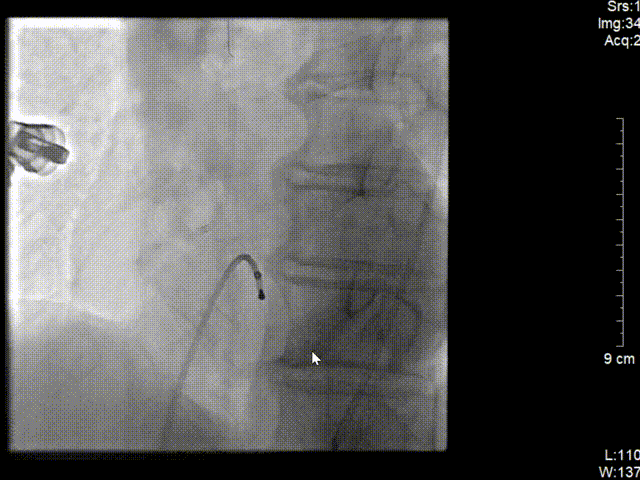

冠脉造影结果(右冠近段病变)

冠脉三支病变 右冠近端完全闭塞病变。

在J型导丝指引下6F JR4.0指引导管于右冠口,行造影提示右冠近段急性闭塞,将SION blue导丝操作通过右冠近端闭塞处并达远段真腔,予2.0*15预扩张球囊行病变处预扩张处理,复查造影可见血栓,予血栓抽吸导管反复抽吸,抽出大量红色血栓。

再次予2.0*15预扩张球囊行病变处预扩张处理,右冠近中置入3.5*40mm药物支架1枚,继续予以3.5*15m后扩张球囊行支架内优化扩张。

复查造影可见右冠远段狭窄80%,并见血栓,予2.0*15预扩张球行右冠远段病变处预扩张,于右冠远段置入2.5*14mm 药物支架1枚,并予以3.0*12mm后扩张球囊行支架内扩张优化。再次造影示右冠狭窄消失,无夹层及残余狭窄,TIMI血流3级。